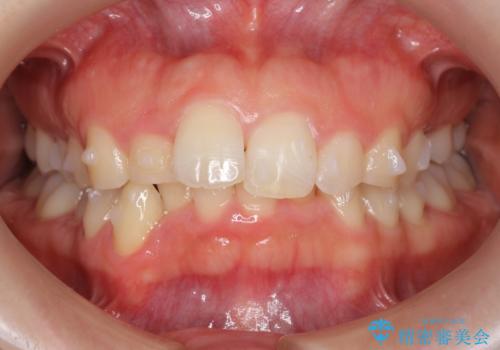

- 前歯のがたがたと出っ歯を主訴に来院。

遠心移動などは行わず、IPRと拡大のみで治療を行いました。

一般的に非抜歯矯正を無理に行うと、口元がモッコリ出てしまうことがあります。しかし、今回は前歯を前に出さないような設定にしており、口元が出ることもありませんでした。